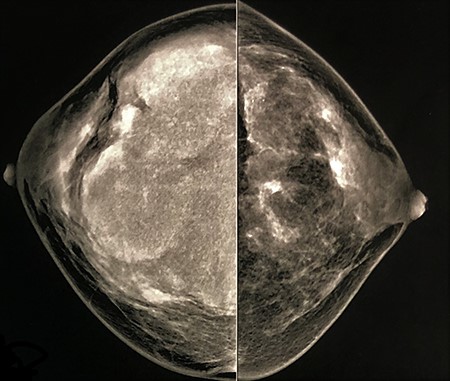

Two years ago, the patient had undergone a mammogram (Fig. 2), which had shown breast asymmetry due to a large lobulated mass with smooth and circumscribed margins.

Mammogram (CC view) performed 2 years ago had shown lobulated mass with smooth and circumscribed margins.